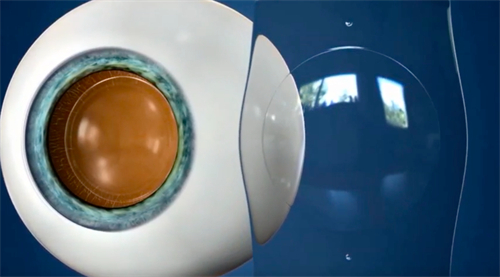

在近视矫正领域,ICL作为一种可靠的手术方式,正逐渐受到越来越多患者的青睐。它不仅能够为高度近视、角膜较薄或无法接受激光手术的患者带来清晰的视界,还因其良好的生物相容性和可逆性而备受赞誉。

ICL晶体植入术是一种通过将特制的软性晶体放置于眼内后房,自然调整光线聚焦位置,从而达到矫正视力的目的。这种晶体由胶原蛋白聚合物制成,具有良好的透氧性和稳定性,能够长期可靠地留在眼内。